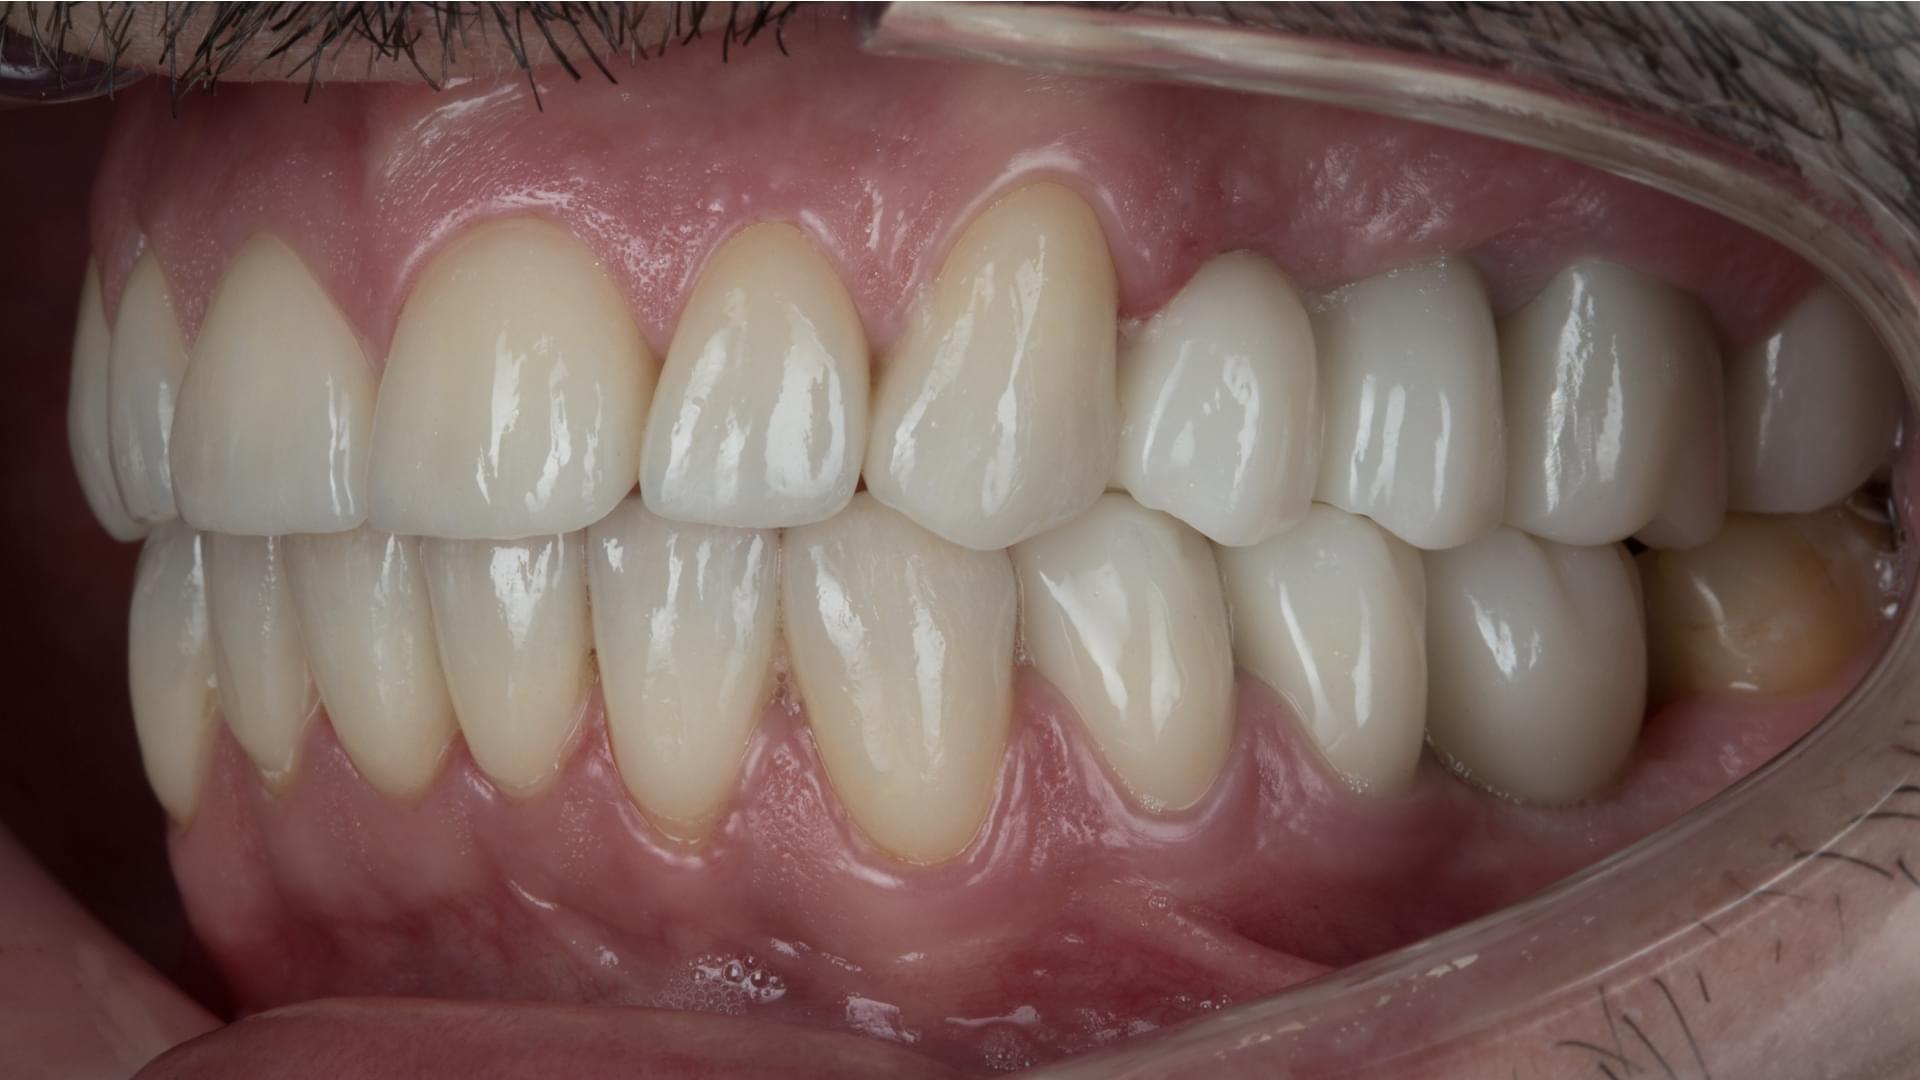

Atunci când are loc devitalizarea unui dinte, acesta trebuie extras din cauza infecției canalului radicular. Pentru restabilirea dintelui, rădăcinile infectate pot fi îndepărtate și înlocuite cu un implant dentar. Acum este posibilă înlocuirea dinților bolnavi cu implanturi și coroane din Zirconiu, și obținerea unui zâmbet natural și estetic, planificat cu ajutorul computerului.

Cea mai eficientă metodă, în cazul pierderii dinților, este înlocuirea acestora cu punți sau implanturi dentare. Pentru a avea niște gingii sănătoase este recomandată inserarea implanturilor dentare peste care, în cele din urmă, se inserează coroanele dentare din Zirconiu, astfel obținând un zâmbet natural și estetic. Toată planificarea are loc cu ajutorul computerului.

Acoperirea dinților cu punți și coroane metalo-ceramice, odată cu trecerea timpului, afectează gingiile și rădăcinile. Atunci când are loc îndepărtarea gingiilor de punțile metalo-ceramice, se descoperă un profil metalic negru și inestetic. De asemenea, are loc acumularea alimentelor și carierea rădăcinilor care susțin capsulele. Acum este posibilă înlocuirea coroanelor și punților cu implanturi dentare, astfel obținând un zâmbet natural și estetic.

Implanturi Dentare 🔥 Cazuri finisate #1